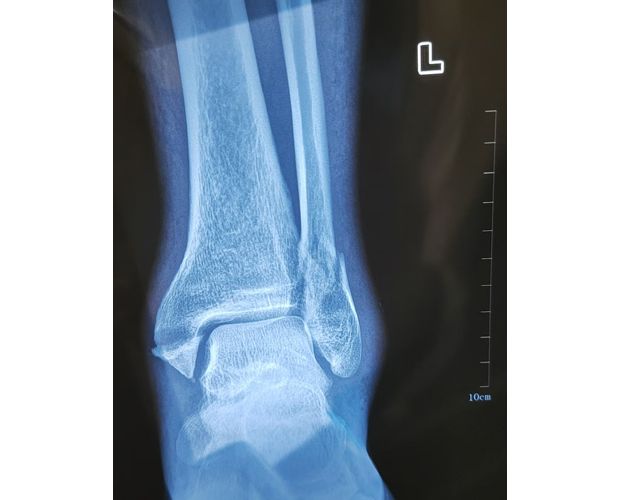

2月4日,何店鎮(zhèn)中心衛(wèi)生院接診一名左踝關(guān)節(jié)外傷患者,經(jīng)影像檢查,確診為左脛、腓骨下段骨折。外科醫(yī)生姜穩(wěn)迅速完成術(shù)前檢查及病情評估,并與患者及家屬深入溝通治療方案。在患者強烈要求于本院進行手術(shù)的情況下,為最大限度保障手術(shù)質(zhì)量與安全,該院特邀請醫(yī)共體牽頭單位——曾都區(qū)人民醫(yī)院脊柱創(chuàng)傷外科專家團隊前來指導(dǎo)。